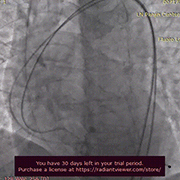

术中影像

主动脉根部造影

导丝顺利跨瓣

TaurusAtlas 20mm球囊

充分预扩张

无明显腰征 无漏

TaurusElite AV23瓣膜

瓣下2mm初始定位

工作位造影 位置满意

冠脉灌注良好

瓣膜最终位置造影

形态良好 无瓣周漏

即刻跨瓣压差为4mmHg